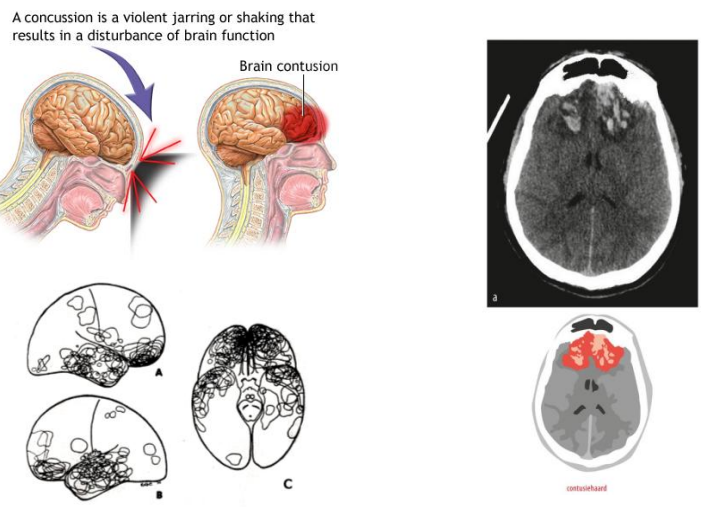

1) Contusio cerebri

matig tot ernstig (hersenkneuzing)

MRI: duidelijke laesies

2) Contusies (kneuzingen)

Waartoe kunnen contusies leiden (primaire letsel)?

(Hemorragische) contusiehaarden / grijzestofletsels